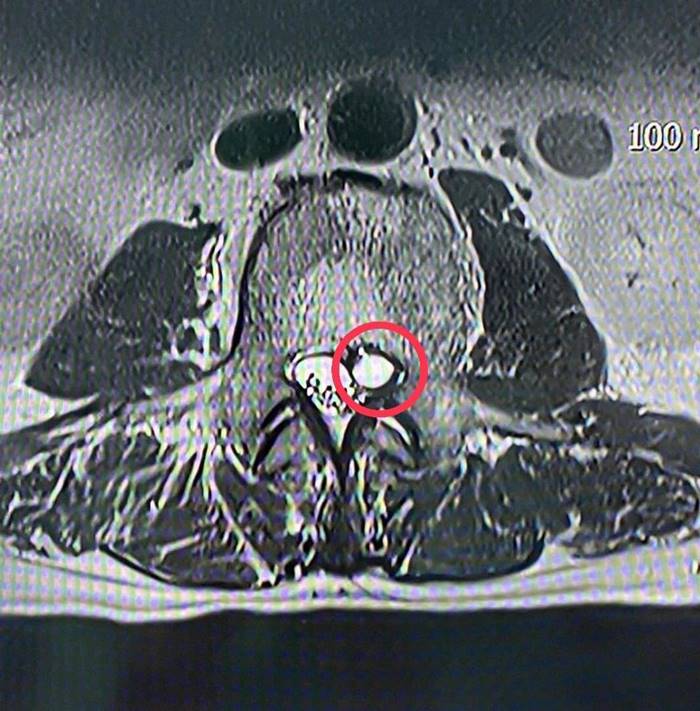

ผลการตรวจสอบจากผู้เชี่ยวชาญด้านศัลยศาสตร์ระบบประสาท คาดว่า เส้นประสาทถูกกดทับ ระดับกระดูกสันหลังข้อที่ 4 จึงส่งตรวจวินิจฉัยโรคเพิ่มเติมด้วย MRI ทำให้เห็นว่ามีก้อนเนื้อไปกดเบียดทับเส้นประสาทอย่างชัดเจน